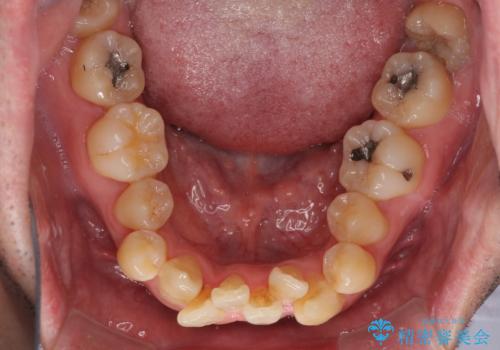

- 前歯のデコボコを気にして来院された患者様です。

叢生の解消とともに、前方に張り出した上顎前歯を引っ込めることを目的とし、上下左右の第一小臼歯4歯を抜歯をしてワイヤー矯正により治療することとしました。